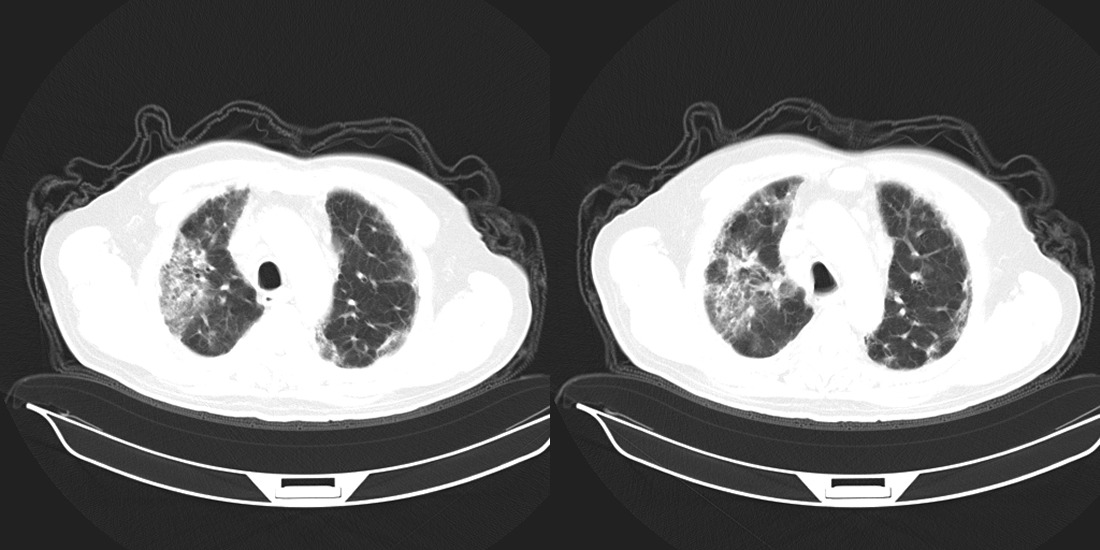

以下是引用zsl6918在2008-2-14 12:15:00的发言:[br]慢支并感染,肺气肿,肺间质纤维化,肺动脉高压。

以下是引用liuyue在2008-2-14 17:25:00的发言:[br]慢支并感染,肺气肿,肺间质纤维化,肺动脉高压 .肺大泡.[br]

以下是引用随光逐影在2008-2-15 11:10:00的发言:[br]1)慢性支气管炎并肺部感染。2)肺间质纤维化。3)肺气肿(多发性肺大泡形成)。4)肺动脉高压。